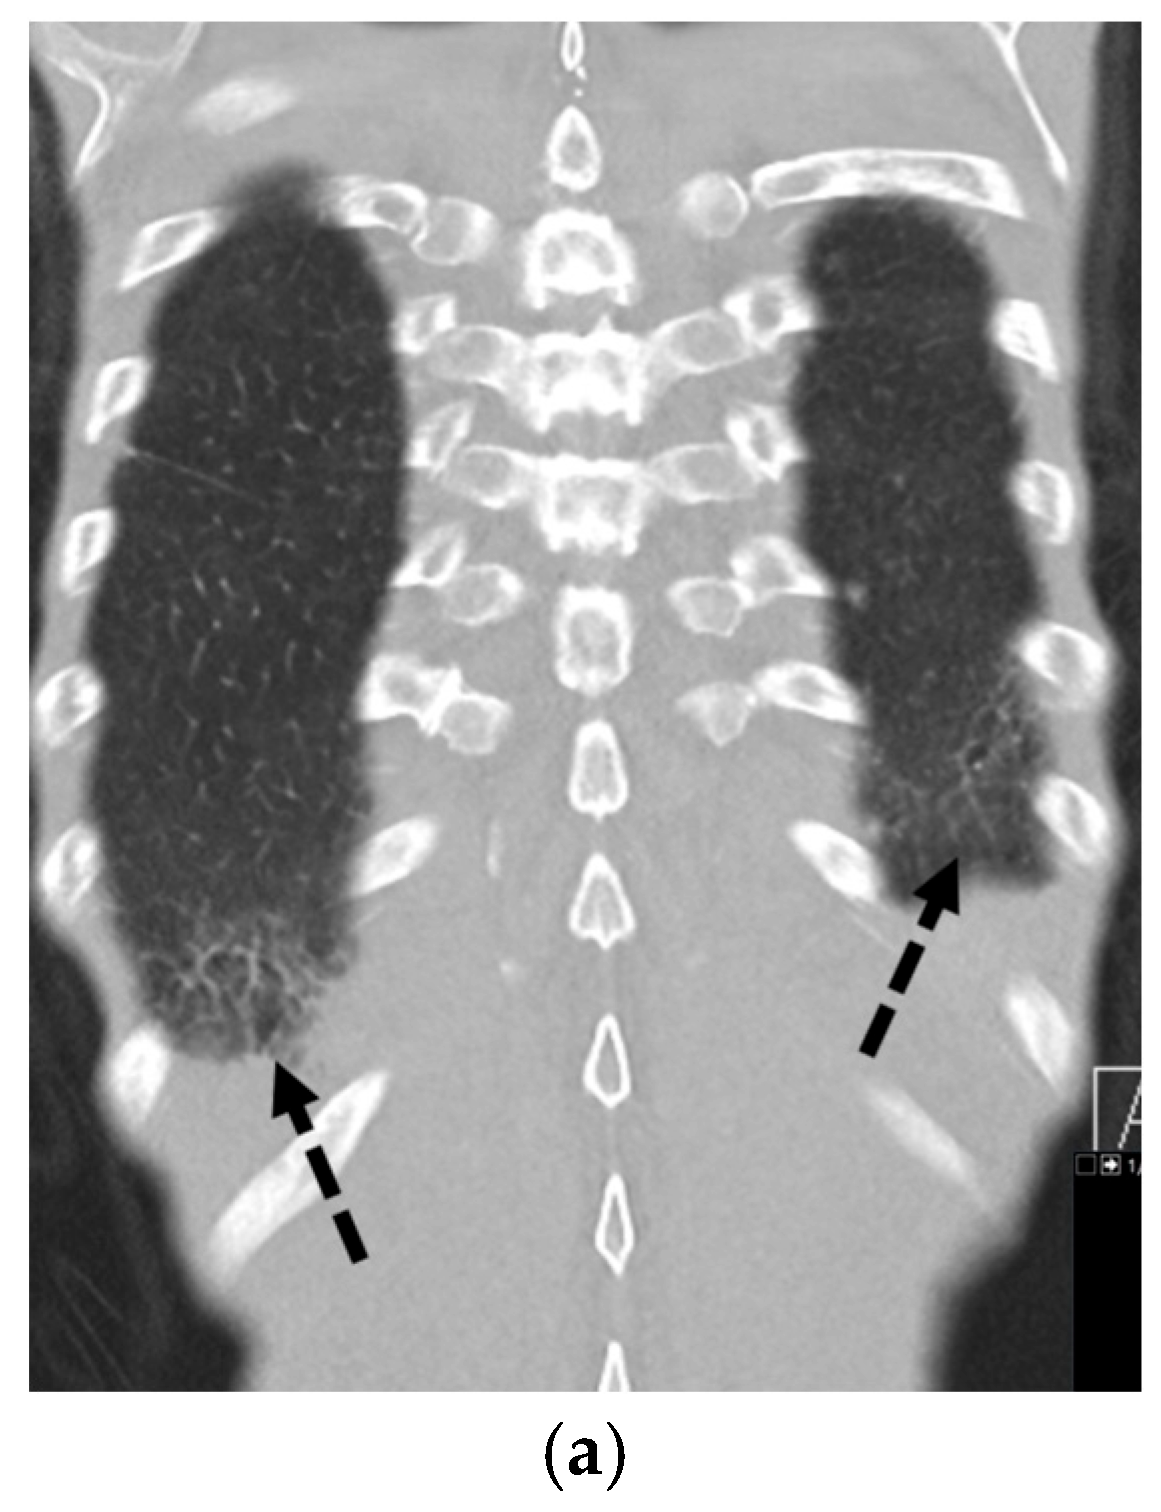

5.5.3. Birt–Hogg–Dubé Syndrome (BHDS)

5.6. Connective Tissue Diseases

5.6.1. Rheumatoid Arthritis

5.6.2. Systemic Sclerosis

5.6.3. Ankylosing Spondylitis

5.6.4. Marfan’s Syndrome

5.6.5. Ehlers–Danlos Syndrome (EDS)